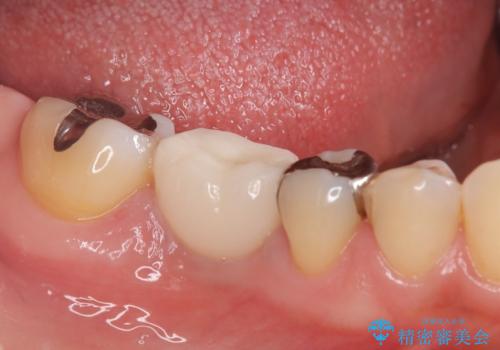

骨の量は十分あったため、比較的短期間で治療は終了しました。

安定した咬み合わせとなり、痛みもなく安心して噛めるようになりました。